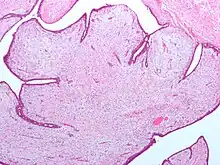

| Fibroepithelial neoplasm (Phyllodes tumor). | |

A fibroepithelial neoplasm (or tumor) is a biphasic tumor. They consist of epithelial tissue, and stromal or mesenchymal tissue. They may be benign or malignant.[1]